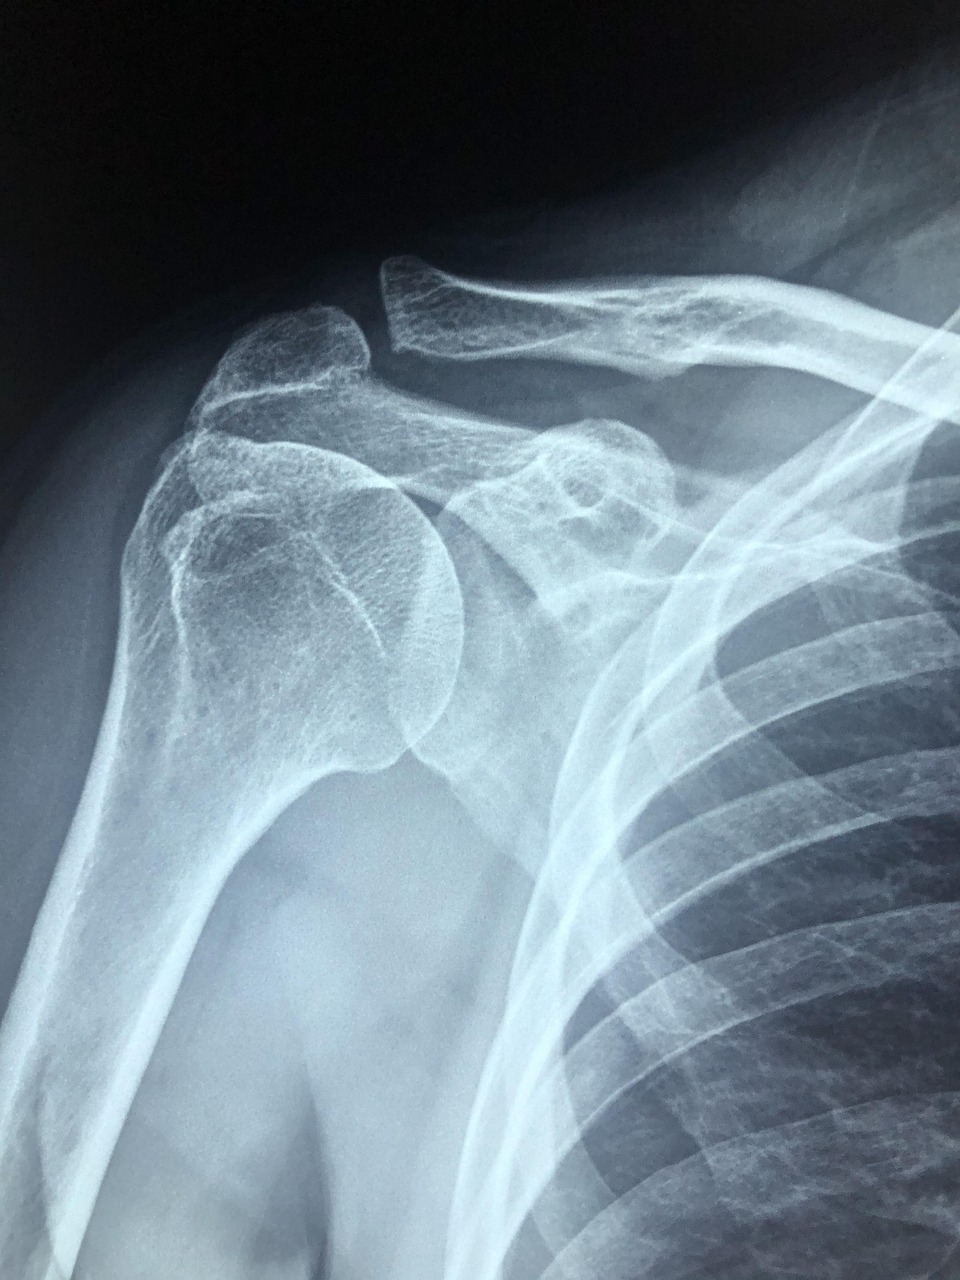

아이들은 활발하게 뛰고 노는 과정에서 골절이나 관절 손상을 흔히 겪습니다. 겉보기에 단순한 골절 같아 보여도, 아이의 뼈는 성인과 달리 성장판이 존재해 치료 방식이 완전히 다르다고 합니다. 따라서 소아 환자는 반드시 소아정형외과 전문의 또는 소아정형외과 전공의가 있는 병원에서 진료받는 것이 안전합니다.

어린이 뼈 끝에는 성장판이 있어 뼈 길이와 모양을 결정합니다. 따라서 뼈 끝 쪽에 골절이 생긴 경우에는 성장판이 손상되었는지 여부를 같이 확인해주어야 하기 때문에 소아정형외과 전문의 가 같이 봐주어야 정확한 판단이 가능합니다. 만약 성장판이 손상되면 팔다리 길이에 차이가 날 수 있으며, 변형이 발생할 수도 있습니다. 성인 정형외과 적으로 접근하여 수술하면 성장 장애를 남길 수 있기 때문에, 성장판 보존을 최우선으로 치료하는 소아정형외과 전문의를 찾아가시는게 좋습니다.